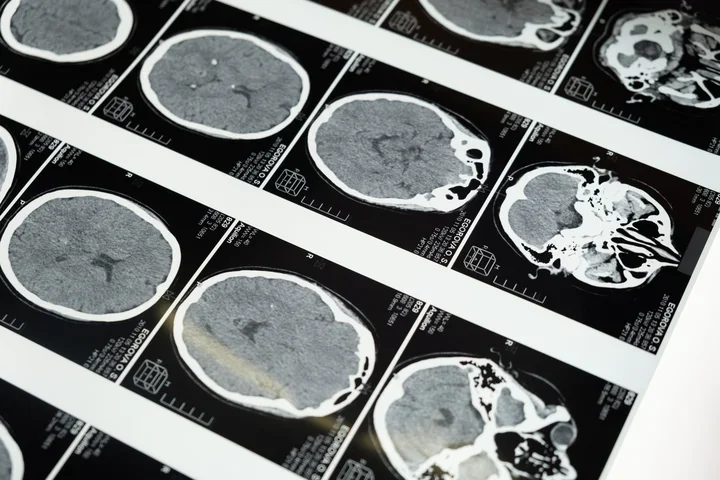

The hereditary cerebellar ataxias are a collection of rare genetic disorders that cause progressive destruction of the cerebellum and subsequent impairment of balance and coordination. Ultimately, this can render patients unable to walk and care for themselves. Although more than 500 genes have already been identified that can cause cerebellar ataxia, the etiologies of up to 50% of affected patients and families still remain unknown.